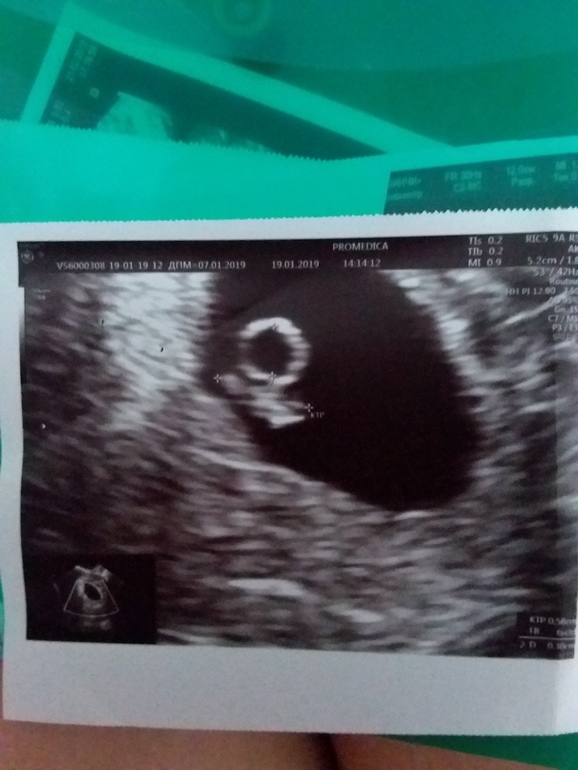

вот наше фото в 6 недель

Я делала в 5 недель и 6 дней - нашли ПЯ в матке. Эмбриона не видно еще было. Переделывала в 6 недель и 5 дней чтоб увидеть эмбрион и сердечко услышать. А с дочкой пошли в 6 недель и 3 дня - тогда уже и крошка была в 5 мм и сердечко стучало.

Ходила в 4,5 к гинекологу - провела осмотр, назначила узи ровно в 6 недель. На узи увидели ПЯ, малыша и сердцебиение, но ктр тогда был очень маленький, кажется 2,4 мм, т.е. я так поняла еще не каждый врач может разглядеть